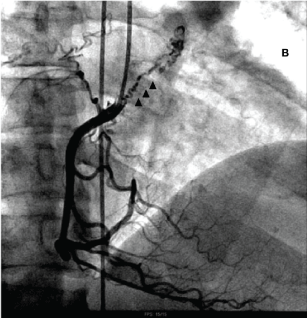

A 42-years-old-male patient presented sudden dyspnoea and was diagnosed with acute PE, and started treatment with warfarin. Despite the treatment, the dyspnoea worsened over the years. He was then referred to our pulmonary hypertension center. On admission, he presented functional class III, pulse oximetry of 90%, severe lower limbs edema. At echocardiography, systolic pulmonary artery pressure was 112 mmHg, with signs of severe right ventricle dysfunction. CT scan demonstrated signs of CTEPH associated with marked bronchial arteries dilation (Figure 1). The right heart catheterization showed mean PAP 60 mmHg, PVR 12.9 W, CO 3.8 L/min. Coronary angiography demonstrated collaterals between the right coronary artery and bronchial circulation (Figure 2). These appeared to contribute to myocardial ischemia, evidenced by a myocardial nuclear scan.

Figure 2: Coronary angiography showing collaterals between the right coronary artery and bronchial circulation.